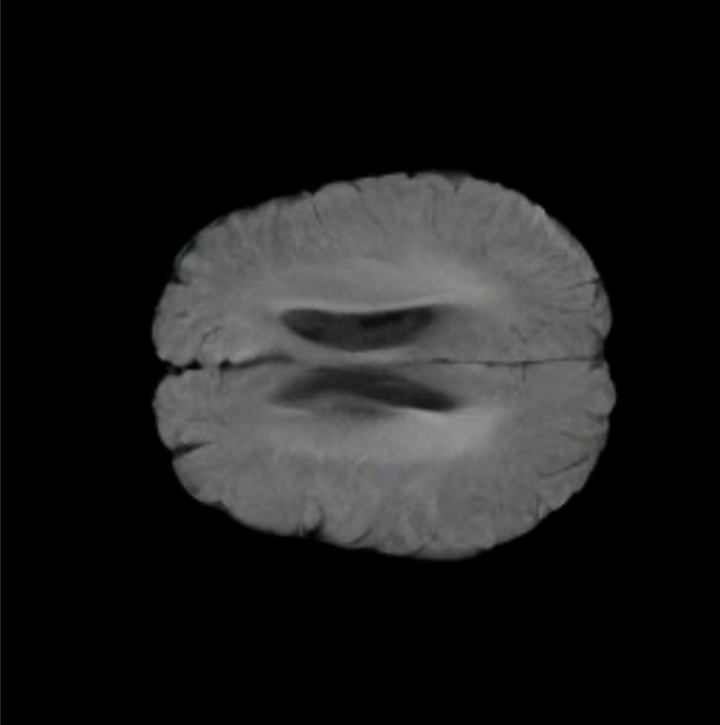

Notably, X-Diffusion achieves state-of-the-art dB for a few input slices while baselines require more than 60 input slices to achieve similar performance (Figure 7). The margin is more than 12 dB PSNR for the 1-slice input in both the BRATS and the UK Biobank benchmarks (see Table 1 and Figure 6). For reference, two randomly sampled MRIs from UK Biobank would have a PSNR of 15.95 dB 0.36 (on 4800 randomly sampled examples). Omitting the preprocessing step of alignment DXA to MRI, leads to a drop of PSNR on average by 2.87 dB (29.01 dB 26.14 dB). The slices from 3D reconstructed volumes at varying depths and axis of rotation, visually match the ground truths for both brain and whole-body scans (see Figures 4 and 5 left). We also plot the error map (Figure 3) and the spread of the error (Figure 5 right) of such X-Diffusion generations to highlight the differences with the ground truth MRIs.

Tumour Information Preservation. For the brain tumor segmentation, we use a Swin UNETR model[28, 70], trained with random rotation, and intensity as data augmentation. On the test set with human ground-truth annotations (), the brain volumes generated from single slice input preserve the volume of the different tumour components (paired t-test, for all 3 classes). In Figure 4, we highlight the tumor profiles of the generated MRIs compared to the ground truth tumour profile. The real MRI Dice score in the test set is 85.15 while the generated MRIs from a single slice have a dice score of 83.09. This shows how the generated MRIs indeed preserve the tumor information and can act as an affordable and informative pseudo-MRI, before conducting an actual costly MRI examination in hospitals. More detailed results are provided in supplementary material.